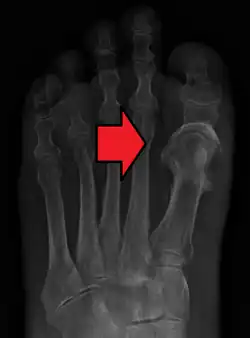

Fat embolism most commonly occurs as a result of fractures of bones such as the femur or pelvis.[3][1] Other potential causes include pancreatitis, orthopedic surgery, bone marrow transplant, and liposuction.[3][2] The underlying mechanism involves widespread inflammation.[3] Diagnosis is based on symptoms.[2]

Orthopaedic injuries, especially fractures of the long bones, are the most common cause of fat embolism syndrome (FES). The rates of fat embolism in long bone fractures vary from 1% to 30%. The mortality rate of fat-embolism syndrome is approximately 10–20%.[7] However, fat globules have been detected in 67% of those with orthopaedic trauma and can reach as high as 95% if the blood is sampled near the fracture site. As the early operative fixation of long bone fractures became a common practice, the incidence of FES has been reduced to between 0.9% and 11%.[6]